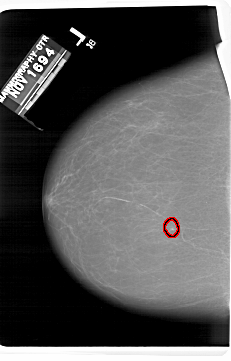

A_1406_1.LEFT_MLO

LEFT_MLO LINES 6136 PIXELS_PER_LINE 4216 BITS_PER_PIXEL 12 RESOLUTION 43.5 OVERLAY

FILE: A_1406_1.LEFT_MLO.OVERLAY

TOTAL_ABNORMALITIES 1

ABNORMALITY 1

LESION_TYPE CALCIFICATION TYPE PUNCTATE DISTRIBUTION CLUSTERED

ASSESSMENT 4

SUBTLETY 4

PATHOLOGY BENIGN

TOTAL_OUTLINES 1

BOUNDARY